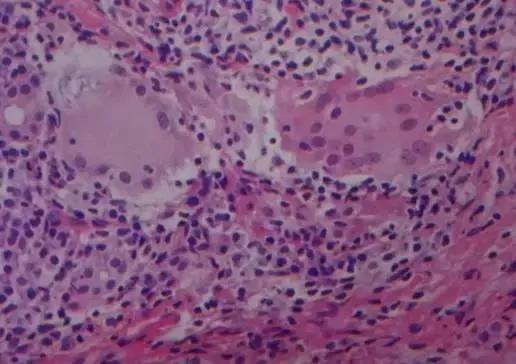

分为特异性炎症和非特异性炎症,特异性炎症是特定致病因素引起的,报告中会出现“肉芽肿性炎”的诊断结果,如结核,麻风,梅毒及真菌等。具体的致病原需要进一步的检测,如特殊染色(银染、PAS染色)等,以结核为例,一般会“建议抗酸杆菌检测或结核PCR 检测”。